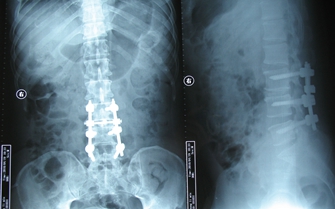

图3.腰椎退变、腰椎间盘突出

图4.腰椎退变、腰椎间盘突出椎弓根钉内固定术后